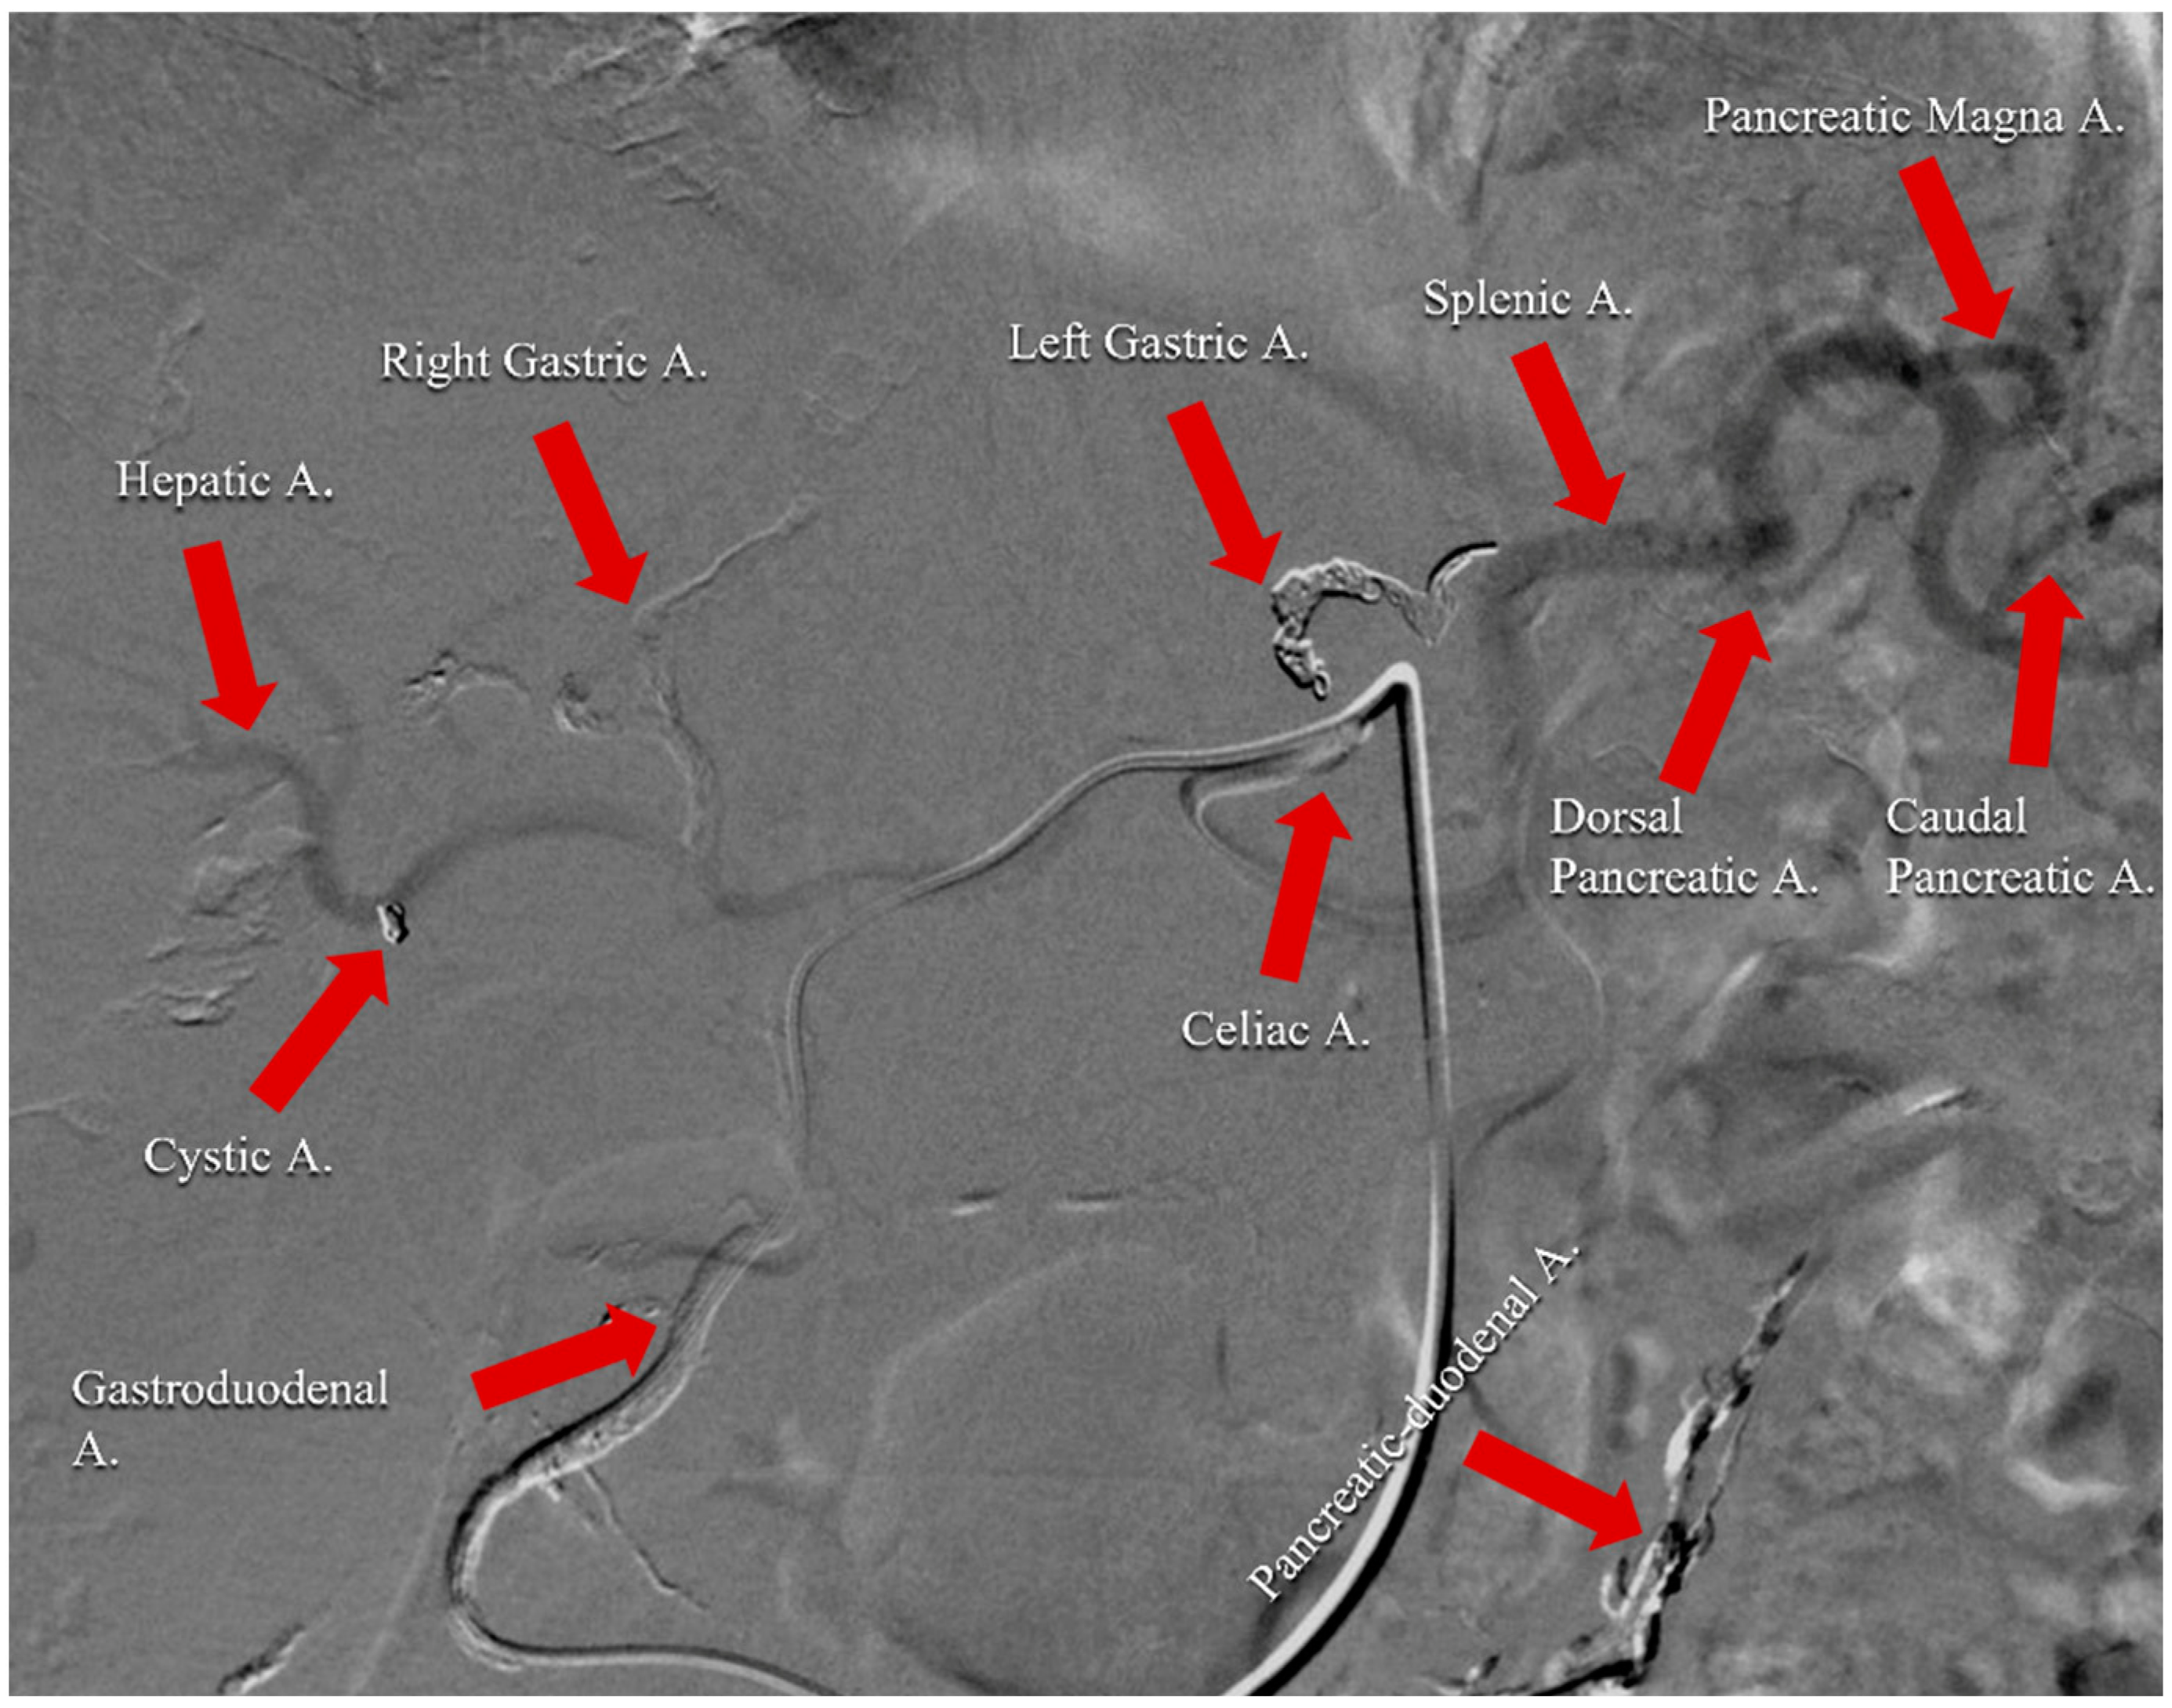

The pancreas is characterized by an extremely variable vascular anatomy and is supplied by several vessels [37]. Specifically, pancreatic parenchyma is vascularized by two main vessels: the celiac artery and the superior mesenteric artery (SMA) [38]. The first feeds the pancreatica magna, dorsal pancreatic, and caudal pancreatic arteries, supplying the pancreatic body and tail [38,39,40]. On the other hand, the pancreatic head is supplied by the pancreaticoduodenal arcade that derives from the junction of the anterosuperior pancreaticoduodenal and the postero-superior-pancreatico-duodenal arteries that originate from the gastroduodenal and the inferior pancreaticoduodenal ones that arise from the SMA [38] (Figure 1A,B).

Figure 1. (A) Angiographic scan representing the vascular anatomy of celiac artery. (B) Angiographic scan representing vascular anatomy of superior mesenteric artery.

Figure 2. Angiographic scan following injection of contrast medium through celiac arterial after the completion of the technical procedure. It represents an example of the vascular remodulation of the celiac trunk for a patient affected by pancreatic cancer with liver metastases. Right gastric, left gastric, gastroduodenal, cystic, and pancreatic-duodenal arteries were embolized with spirals and coils to avoid perfusion of the stomach, duodenum, and gallbladder. Infusion catheter was fixed into gastroduodenal artery.